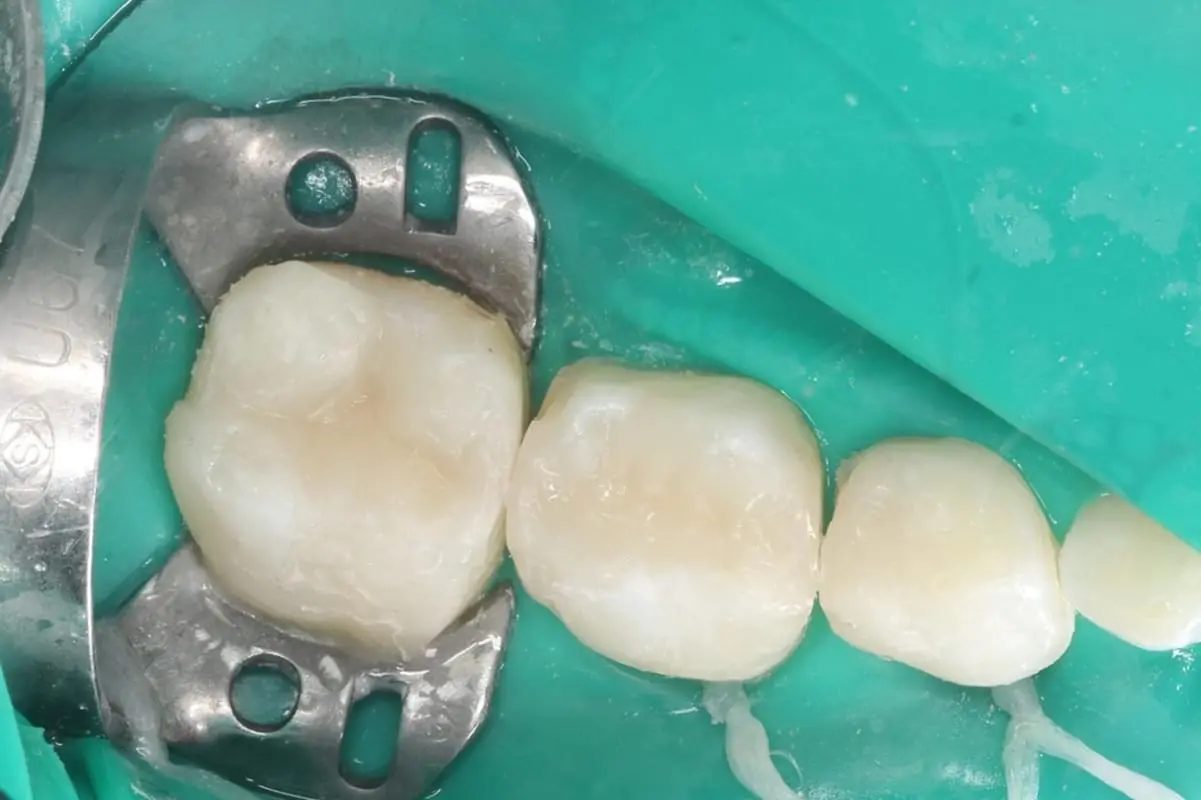

В нашому курсі ми зробили акценти саме на лікуванні карієсу у дітей, зосередились на особливостях карієсології саме у дітей. Ми висвітлюємо і детально розбираємо ці особливості, починаючи від класифікації, особливостей препарування та підбору реставраційних матеріалів, технік відновлення твердих тканин і до мінімально інвазивних методик в дитячій стомтаології. На відеодемонстраціях ми детально демонструємо етапи і послідовність відновлення уражених твердих тканин різних груп зубів у дітей, що допоможе максимально освоїти тематику карієсології та робить курс максимально практичним.

• Модуль 8. Техніки відновлення твердих тканин тимчасових і постійних зубів у дітей.

• Модуль 10. Відеодемонстрація відновлення дефекту 1 класу за Блеком тимчасових молярів композиційним матеріалом на фантомі.

• Модуль 11. Відеодемонстрація відновлення дефекту 2 класу за Блеком тимчасових молярів композиційним матеріалом на фантомі.

• Модуль 14. Клінічна відеодемонстрація відновлення дефекту 1 класу за Блеком тимчасових молярів композиційним матеріалом.

• Модуль 15. Клінічна відеодемонстрація відновлення дефекту 2 класу за Блеком тимчасових молярів композиційним матеріалом.

• Модуль 16. Клінічна відеодемонстрація дефектів тимчасових різців композиційним матеріалом.

• Модуль 17. Клінічна відеодемонстрація відновлення жувальної поверхні постійного шостого зуба.